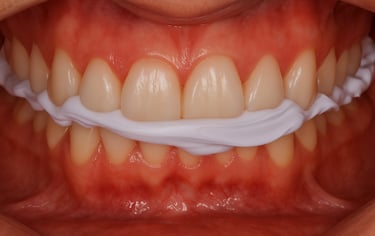

Na prática clínica, o uso do DVR-Sensy resulta em dispositivos com alto grau de compatibilidade fisiológica e menor necessidade de retrabalho clínico.

O equilíbrio oclusal obtido tende a ser mais previsível, pois deriva de uma posição mandibular não induzida.

Essa previsibilidade se traduz em melhor adaptação inicial, menor necessidade de ajustes corretivos e maior estabilidade funcional no uso prolongado.

Esses resultados decorrem diretamente do controle fisiológico do registro, e não de ajustes compensatórios pós-fabricação.